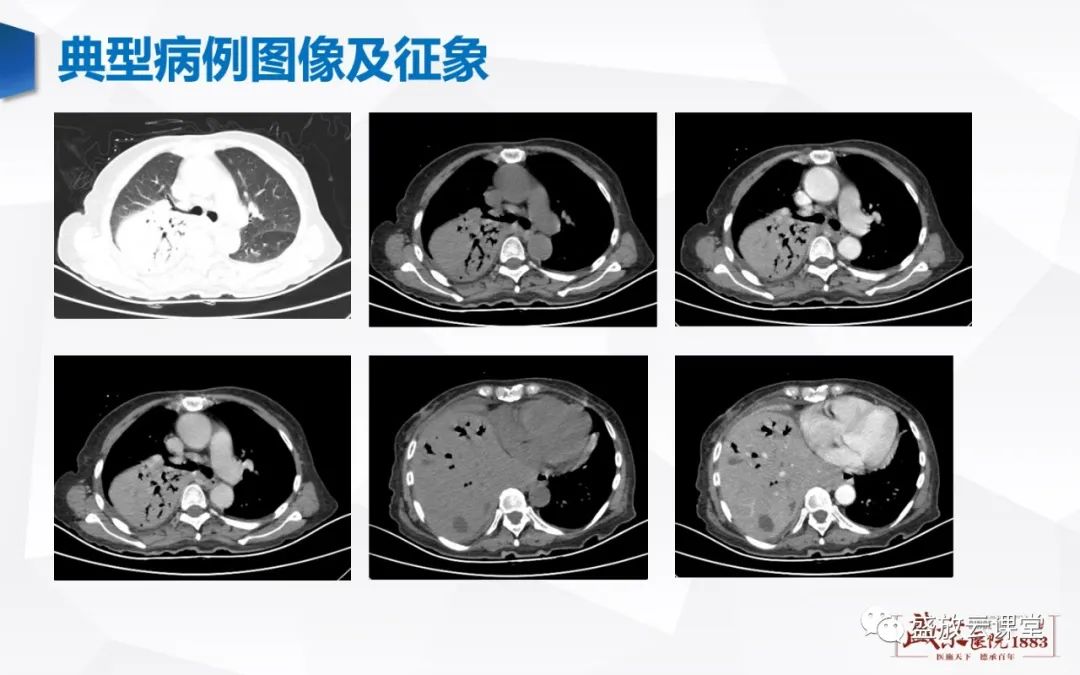

【病例】肺淋巴瘤(MALT)一例CT影像-1 【病例】肺淋巴瘤(MALT)一例CT影像-2

【病例】肺淋巴瘤(MALT)一例CT影像-3 【病例】肺淋巴瘤(MALT)一例CT影像-4

【病例】肺淋巴瘤(MALT)一例CT影像-5 【病例】肺淋巴瘤(MALT)一例CT影像-6